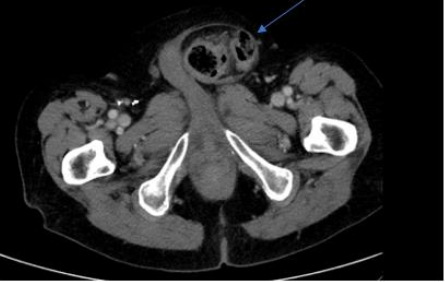

On examination, there was obvious protrusion of a large ventral hernia from a previous midline laparotomy. The hernia was tender and not reducible. Laboratory investigations showed WCC within normal limits at 10.5x109/L and a mildly elevated CRP of 20.5. CT-abdomen showed sigmoid diverticulitis within a large ventral hernia with no evidence of bowel obstruction or ischaemia (Figure. 2).

Figure 2: Axial view of CT-abdomen/pelvis showing incarcerated ventral hernia